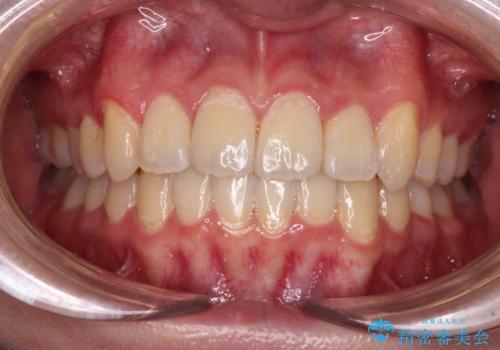

【モニター】左右のクロスバイトをインビザラインできれいに改善